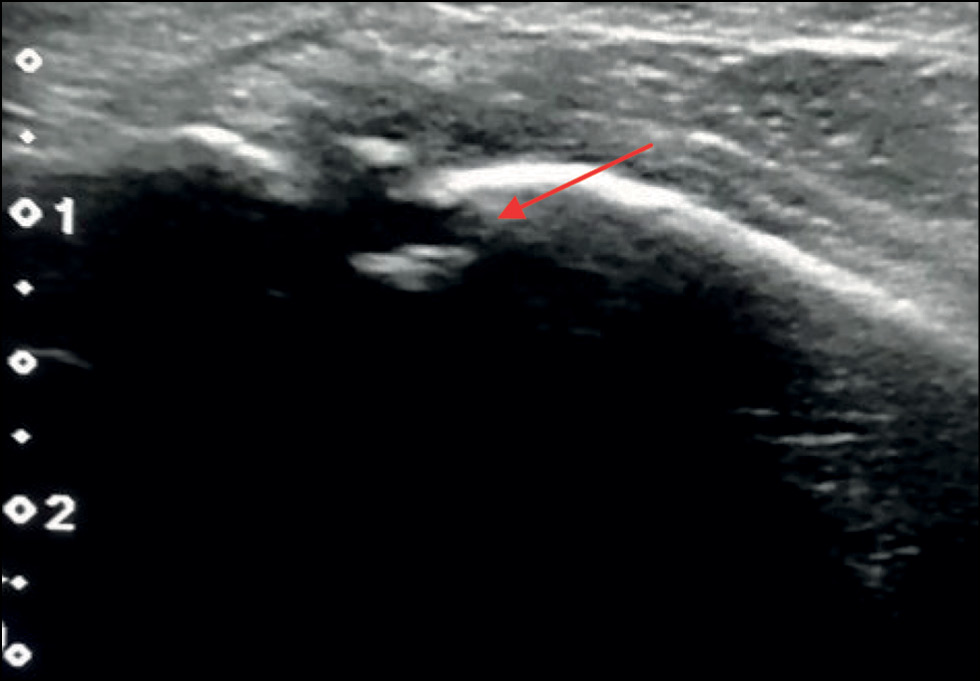

Пациентка А.А., 13 лет, диагноз: «Закрытый эпифизарный перелом переднего бугорка правой большеберцовой кости со смещением. Разрыв дистального межберцового синдесмоза». Ребёнок поступил в отделение спустя 3 нед с момента травмы с жалобами на боль при ходьбе и чувство нестабильности в правом голеностопном суставе. Травма получена в результате непрямого супинационно-инверсионного механизма. Первоначально пациентке поставлен диагноз: «Дисторсия связочного аппарата правого голеностопного сустава», рекомендована иммобилизация на 2 нед полужёстким ортезом. Клинически наблюдали пастозность в области правого голеностопного сустава, локальную болезненность при пальпации. Для определения повреждения межберцового синдесмоза использовали клинические тесты: тест сжатия и тест внутренней ротации стопы. Оба теста оказались положительными. Пациентке было выполнено рентгенологическое исследование в прямой и боковой проекции (рис. 1). Для уточнения наличия повреждения межберцового синдесмоза дополнительно сделаны рентгенологические снимки в синдесмозной проекции в сравнении со здоровым суставом под нагрузкой (рис. 2). В связи с тем, что клинически и рентгенологически обнаружили признаки повреждения межберцового синдесмоза, для уточнения характера повреждения использовали метод УЗ-диагностики. Обнаружены свободный костный фрагмент в проекции межберцового промежутка и наличие анэхогенных включений в области вплетения связки, что служит достоверным признаком разрыва. Поскольку были найдены достоверные признаки разрыва, и имелся выраженный болевой синдром, проба с наружной ротацией стопы не проводилась (рис. 3).

Рис. 3. Ультразвуковoе исследование дистального межберцового синдесмоза пациентки А.А. Костный фрагмент и признаки разрыва связки.

Fig. 3. Ultrasound examination of distal tibiofibularis ligaments. Bone fragment and signs of ligament rupture.